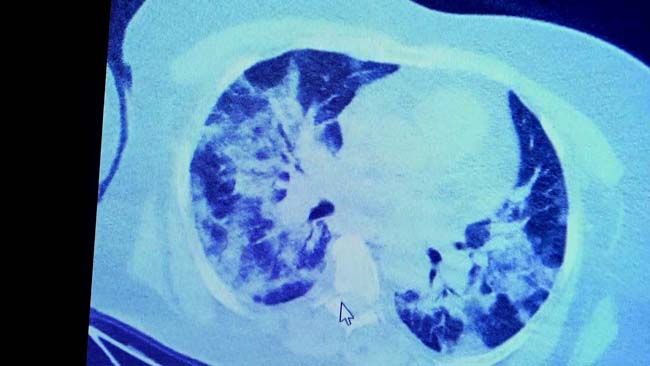

VM Medical Park Samsun Hastanesi’nde görev yapan Göğüs Hastalıkları Kliniği’nden Prof. Dr. Şevket Özkaya da bir hafta ilaç kullanmayan bir pozitif hastanın akciğer tomografisini inceledi. Hasta pozitif haldeyken ilk akciğer tomografisine bakıldı. Tomografide akciğerlerdeki tutulmanın az olduğu gözlemlendi. Akabinde aynı hastanın verilen ilaçları kullanmamış ve 1 hafta boyunca tedaviye uymamış haldeki akciğer tomografisine bakıldı. Sonuç ise ilaç kullanımının önemini ortaya çıkardı. Hastanın akciğer tomografisinde yaygın buzlu camların ve hava yollarının hava yerine ciddi şekilde sıvı ile dolduğu gözlemlendi.

Akciğer tomografisinde oluşan değişim ile ilgili bilgi veren Prof. Dr. Şevket Özkaya, "Ekranda 55 yaşında bir kadın hastamızın filmini görüyorsunuz. Bu kadın hastamız acil servisimize ateş şikâyetiyle geldi ve korona virüsünden şüphe ettik. Testini yaptığımızda ise testin sonucu pozitif geldi. Tomografi çektiğimiz zaman akciğerlerinde henüz ciddi bir tutulum görünmezken hastamız 55 yaşında olduğu için her an ilerleyebilir korkusuyla Sağlık Bakanlığımızın önerdiği ilaçları ve reçeteyi hastanemizden kendisine verdik. Hasta kendini evde karantinaya aldı fakat sonradan öğrendik ki tereddüt ettiği için ilaçlarını kullanmayarak kendini evde tedavisiz bırakmış. Yaklaşık bir hafta sonra aynı hasta acil servisimize bu sefer solunum yetmezliği şikâyetiyle geldi. Solunum yetmezliği gelişince hastanın akciğer tomografisinde ‘buzlu cam’ dediğimiz ve daha ileri konsolide alanların oluştuğunu gördük. Yaygın akciğer harabiyeti dediğimiz bir tablo oluşmuştu. Bu durumda hastada solunum yetmezliği olduğu için yoğun bakıma almak zorunda kaldık" dedi.